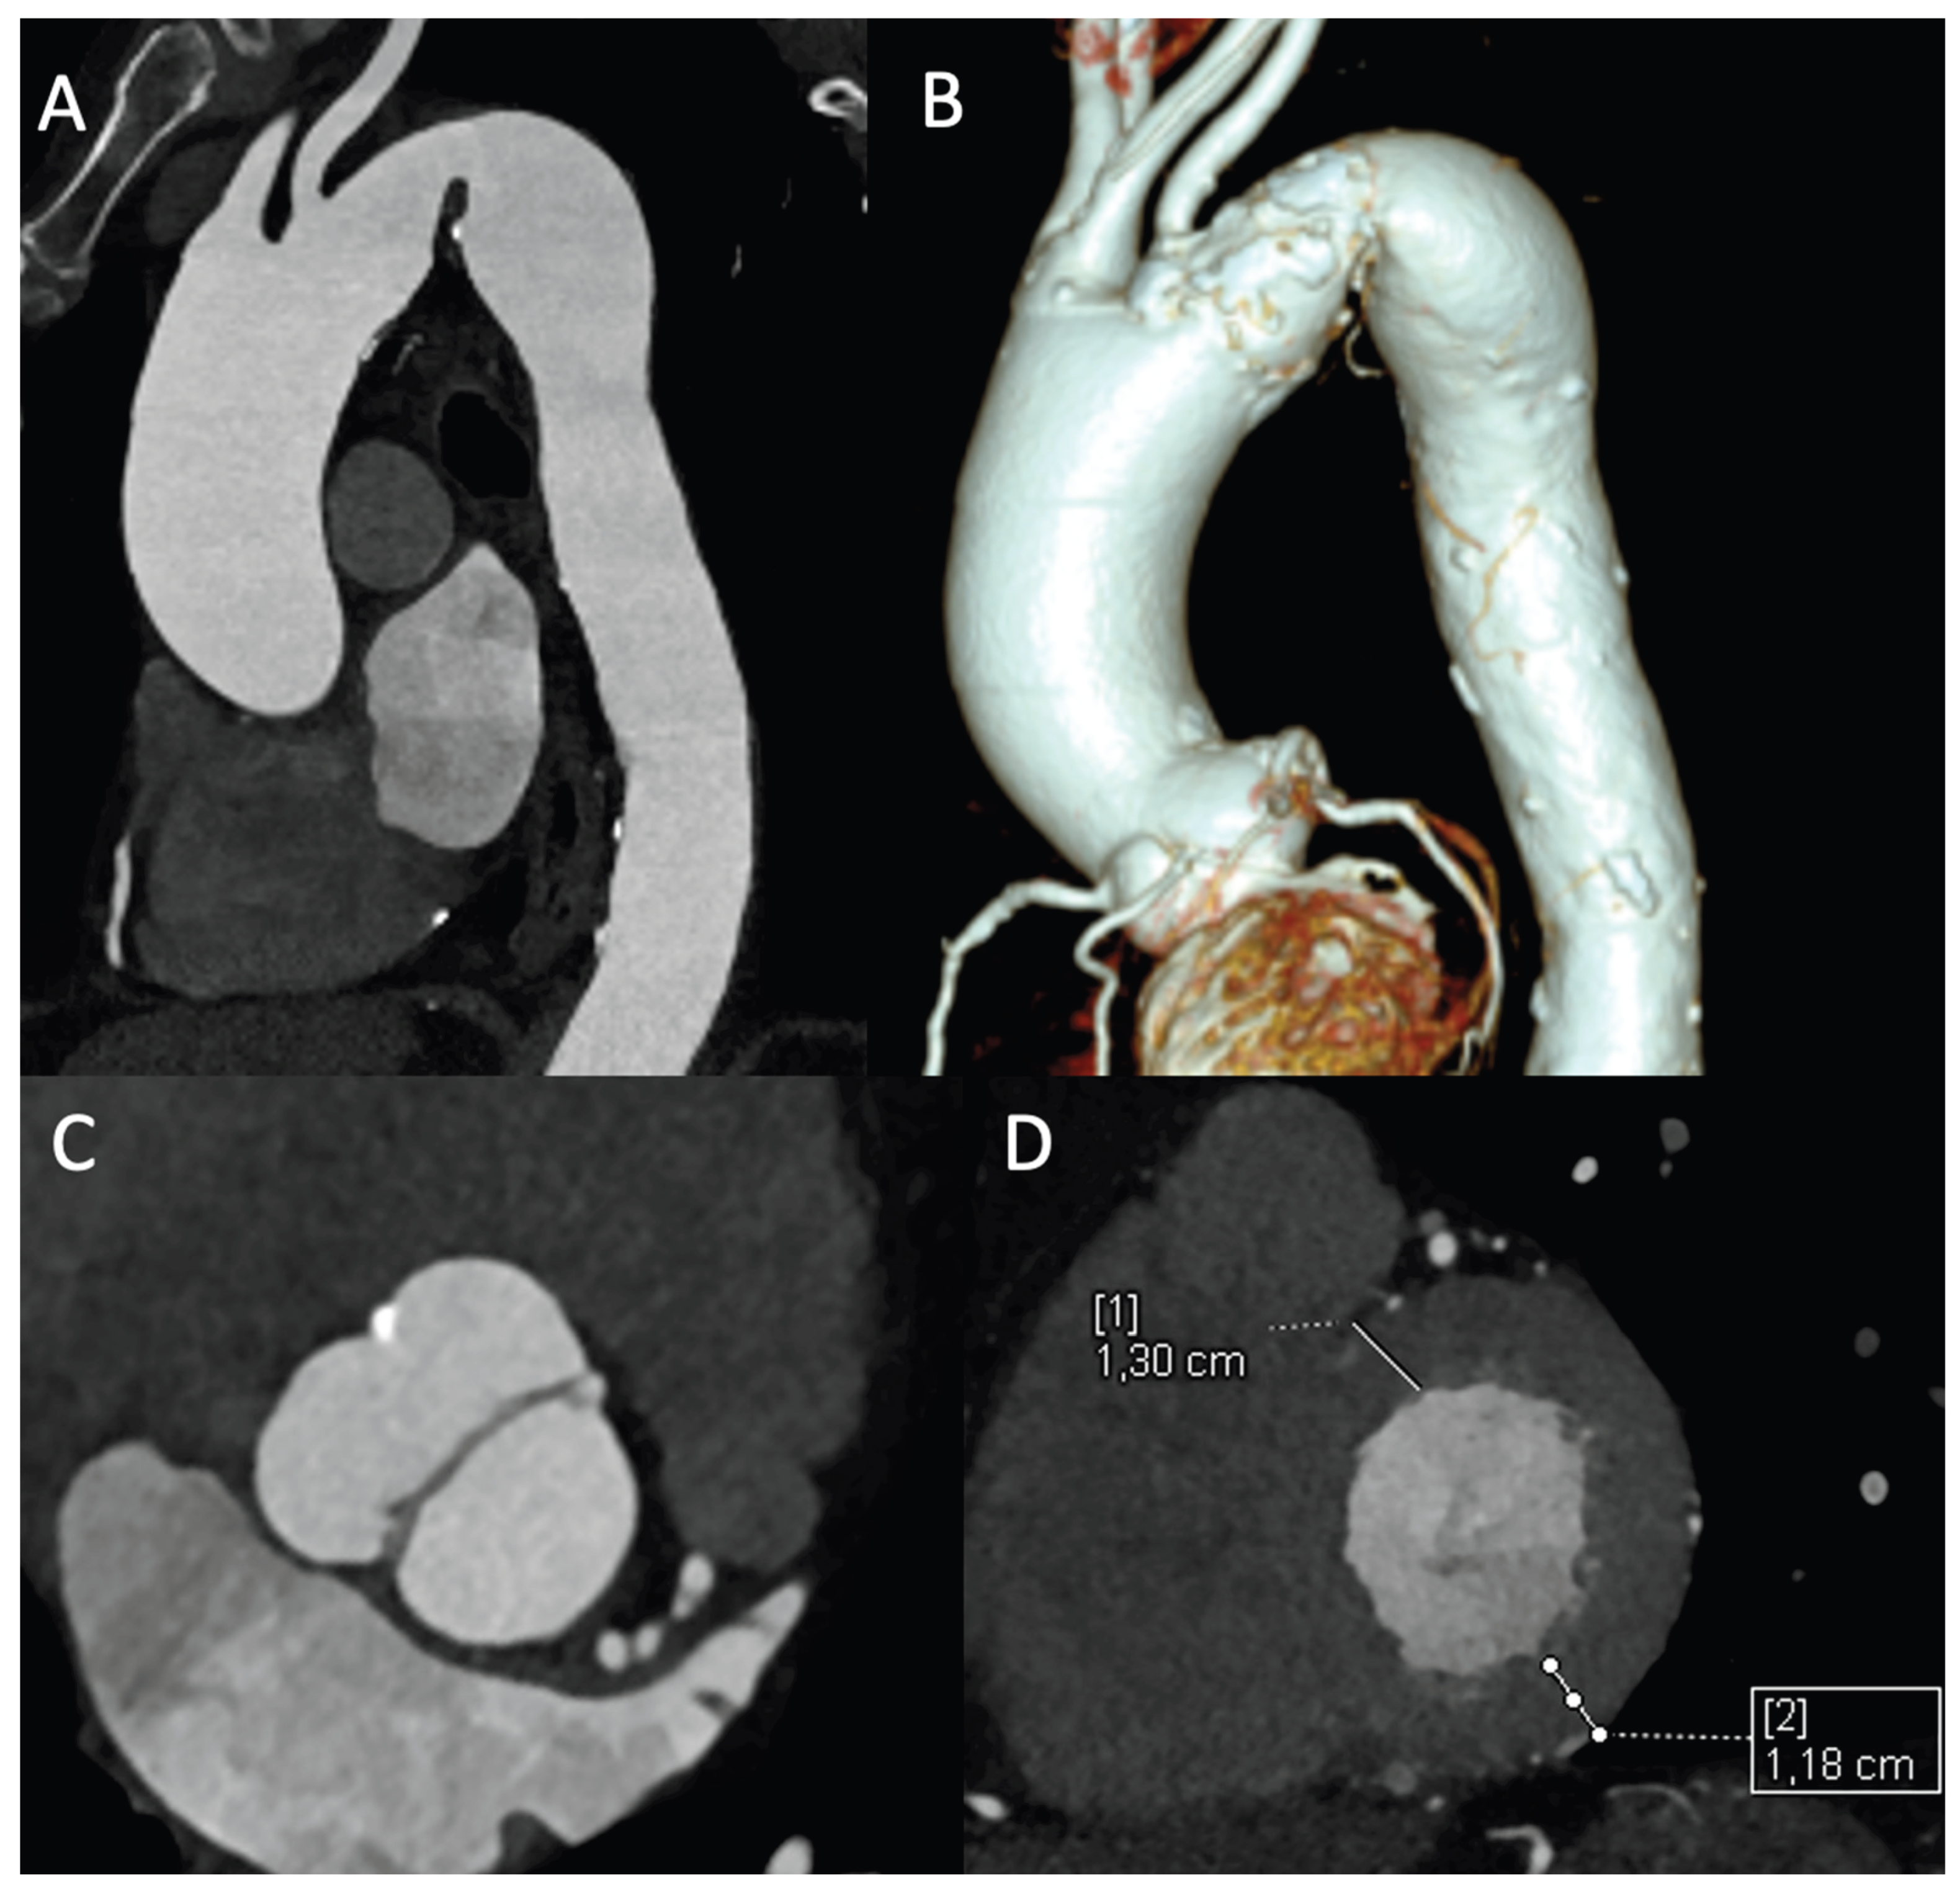

Suprasternal view allows functional evaluation with continous-wave doppler (CW) to assess peak systolic velocity (>2 m/s) and peak pressure gradient (> 20 mmHg) across the CoA-site and pulsed-wave doppler demonstrating prolonged diastolic flow (diastolic tail) with high velocity (> 1 m/s) due to downstream obstruction [23] Subcostal view shows delayed (> 50 ms from ECG R wave) and reduced (< 55 cm/s) systolic upstroke velocity and persistence of anterograde diastolic flow in distal thoracic and upper abdominal aorta [22] (Figure 1)

Figure 1. Assessment of aortic coarctation by TTE. A. Aortic arch color imaging with turbulent flow in suprasternal window. B. Narrowing of the isthmus diameter (with arrow) compared to proximal aortic arch (ratio 0.4) in suprasternal window for anatomical assessment C. Continous Doppler showing peak systolic velocity (>2 m/s) and peak pressure gradient (> 20 mmHg) accross the narrowing site for functional assessment of significant CoA gradient. D. CoA indirect finding of LV hypertrofic remodelling.